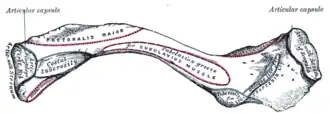

Left clavicle. Inferior surface.

Left clavicle. Inferior surface. -